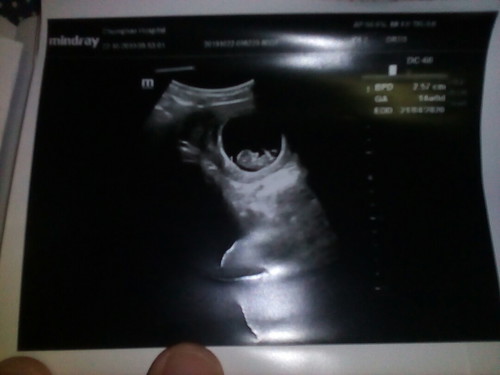

14 สัปดาห์เป๊ะพอดี แต่ดูจากรูปน้องตัวเล็กเกินไปมั้ยค้ะ ต้องทำอย่างไร

ไม่เล็กค่ะ รูปซาวด์ที่ดูใหญ่เพราะหมอซูมจะได้เห็นชัดๆค่ะ

เล็กเกินไปไหม ต้องถามคุณหมอค่ะ ตอนซาวด์ได้ถามไหมคะ?

ไม่ได้ถามเลยค่ะ แค่รู้ว่าน้องหัวใจเต้นยุก็โล่งแล้ว เพราะเคยเป็นท้องลมค่ะ